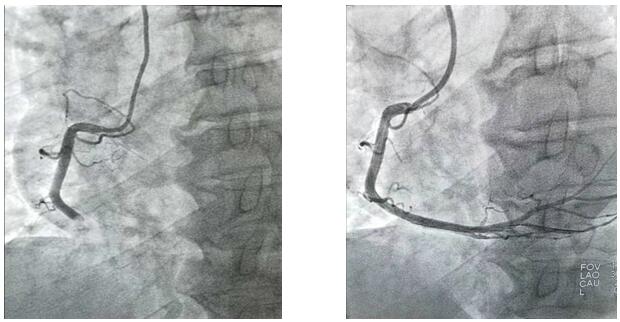

2019年10月1日凌晨1點(diǎn)左右,興平市人民醫(yī)院將一位急性心梗病人送至我院,患者胸痛5小時(shí)并伴有大汗,心電圖顯示ST段呈弓背向上型抬高,出現(xiàn)寬而深的Q波和T波倒置。心肌酶及肌鈣蛋白升高。心血管病院值班二線立即通知導(dǎo)管室值班醫(yī)生。“導(dǎo)管室已啟動(dòng)”,一場與死神的博弈即將開始,醫(yī)護(hù)人員“飛毛腿”式趕到導(dǎo)管室,護(hù)士開始了準(zhǔn)備工作,“液體已配好、除顫儀處于備用狀態(tài)、急救藥品準(zhǔn)備完畢”的同時(shí),隨著技師“趕快帶病人”。醫(yī)護(hù)人員穿上近30斤重的鉛衣、洗手、戴口罩,一場沒有硝煙的戰(zhàn)爭正式開始了,消毒、穿刺、造影.....手術(shù)緊張而有序的進(jìn)行著,經(jīng)過一小時(shí)左右的奮力搶救,病人終于脫離了危險(xiǎn)。安全送至CCU后,醫(yī)護(hù)人員此時(shí)已經(jīng)筋疲力盡,身上的衣服也已經(jīng)濕透,但大家還是會(huì)共同探討手術(shù)的過程。

凌晨3點(diǎn),手術(shù)室終末消毒工作剛剛結(jié)束,“滴滴滴……”胸痛中心來電,啟動(dòng)導(dǎo)管室,醫(yī)護(hù)人員再次穿上鉛衣沖向?qū)儆谧约旱奶厥鈶?zhàn)場……10月1日、10月2日、10月3日、10月4日、10月5日、10月6日,我們完成PTCA支架置入術(shù)、冠狀動(dòng)脈內(nèi)溶栓術(shù)、PTCA腔內(nèi)成型術(shù)、臨時(shí)起搏器置入術(shù)、冠狀動(dòng)脈內(nèi)左室造影術(shù)及冠狀動(dòng)脈內(nèi)血管造影術(shù)共計(jì)心臟介入手術(shù)35例。我們永不停息的穿梭與手術(shù)間,平凡的本職工作中,與死神賽跑.....挽救了無數(shù)名生死垂危的患者,解除患者病痛的同時(shí),還您一個(gè)完整、幸福的家!